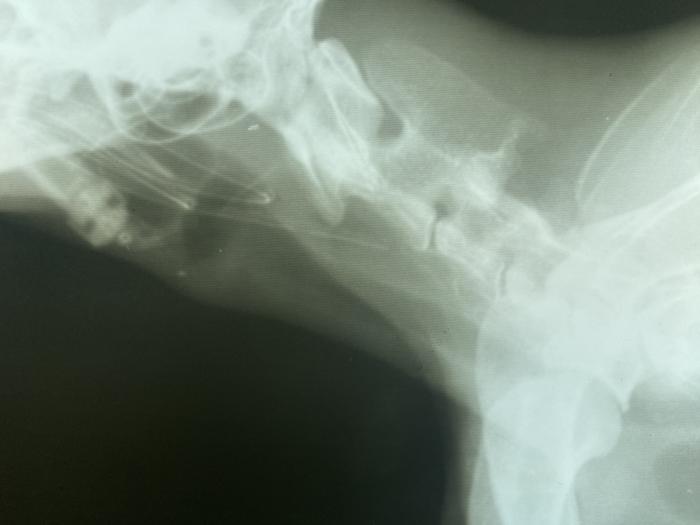

Hay una demora del tercer procedimiento, indicado inicialmente cada 2-4 días, la cual desencadena una complicación no esperada. Originando un aparente cierre completo de la estenosis cervical craneal, el paciente no tolera líquidos ni comidas. La tutora acude a consulta, informando que aparentemente estaría broncoaspirando. Realizamos estudios de imágenes radiográficas, donde se descarta esta posible complicación, pero determinamos el cierre de la estenosis esofágica cervical craneal, con la imposibilidad de colocación de sonda nasoesofágica (sonda de 3.5 F). Luego de varios intentos infructuosos, se comunica este impedimento, con el cual determinamos la estenosis completa, o de mayor gravedad impidiendo el paso de todo tipo de sonda (Figura 6A-C).

Figura 6. (A) Proyección laterolateral de tórax donde descartamos una posible broncoaspiración. (B) Imagen radiográfica obtenida durante el intento de colocación de una nueva sonda de alimentación esofágica. (C) Se puede evidenciar como la punta de la sonda ingresa por el esfínter esofágico anterior. Dilatación del segmento inicial del esófago cervical y caudal a la misma, disminución de la luz esofágica compatible con una estenosis severa.